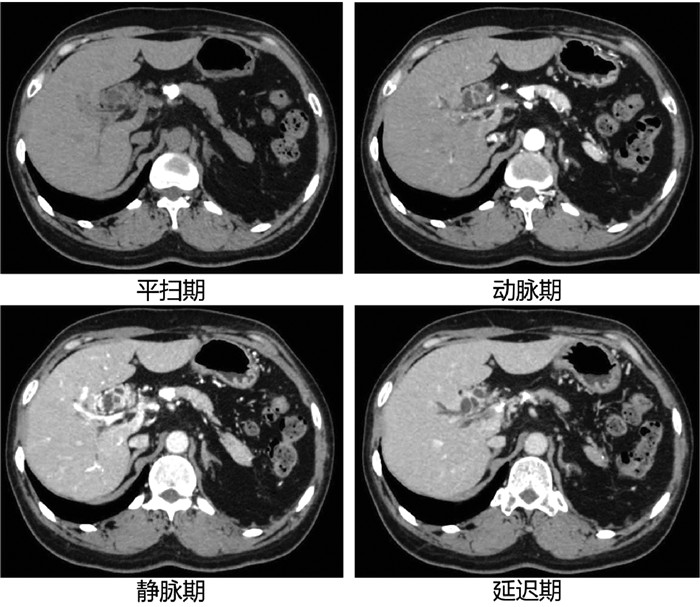

胰腺内副脾误诊为胰腺神经内分泌肿瘤1例报告

夏旭翔, 吕国悦, 仇晓桐, 邱伟

2022, 38(2): 436-438. DOI: 10.3969/j.issn.1001-5256.2022.02.036

摘要(1186) HTML (864) PDF (2885KB)(59)

摘要: